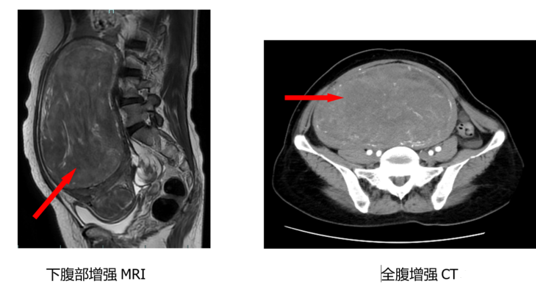

医生一查体,发现她腹部的包块几乎占据了整个盆腔及下腹,上缘达脐上三指。马上安排B超检查,报告提示:子宫多发肌瘤,较大者大小约294mm*100mm*235mm,内呈旋涡状,周边及内部见血流信号。

医生考虑,巨大子宫肌瘤可能性大,性质不明,且康女士为绝经后女性,伴有压迫症状,任其发展可能会影响全身状况,所以建议她尽快入院完善进一步检查并行手术切除。入院后,由于康女士既往患有20多年的糖尿病,且曾有腹部手术史,再加上肿瘤巨大,压迫周围组织,手术的难度和风险明显增加。于是妇科主任助理、副主任医师裘桂静组织团队为其制定了详细的手术方案。

经过妇科医护充分的术前准备,在放射科的影像支持、全科医学科的血糖管理、麻醉手术部的保驾护航下,裘桂静主任带领团队顺利完成了手术。2个小时,100ml的出血,20cm的巨大肌瘤被完整切除,困扰康女士10余年的问题终于得到了解决。